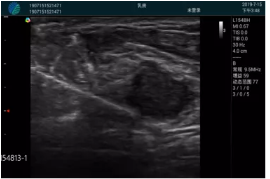

清晰顯示腺體內(nèi)低回聲快影,邊界清晰,包膜較光滑

確定進(jìn)針路徑并實(shí)時(shí)監(jiān)測(cè)抽吸針與腫塊位置關(guān)系

抽吸針進(jìn)入腫塊內(nèi)部進(jìn)行旋切

抽吸過(guò)程中可見(jiàn)腫塊明顯縮小,并根據(jù)腫塊位置改變針道位置

抽吸旋切后再進(jìn)行超聲復(fù)查,原腫塊區(qū)域未見(jiàn)殘留組織及出血